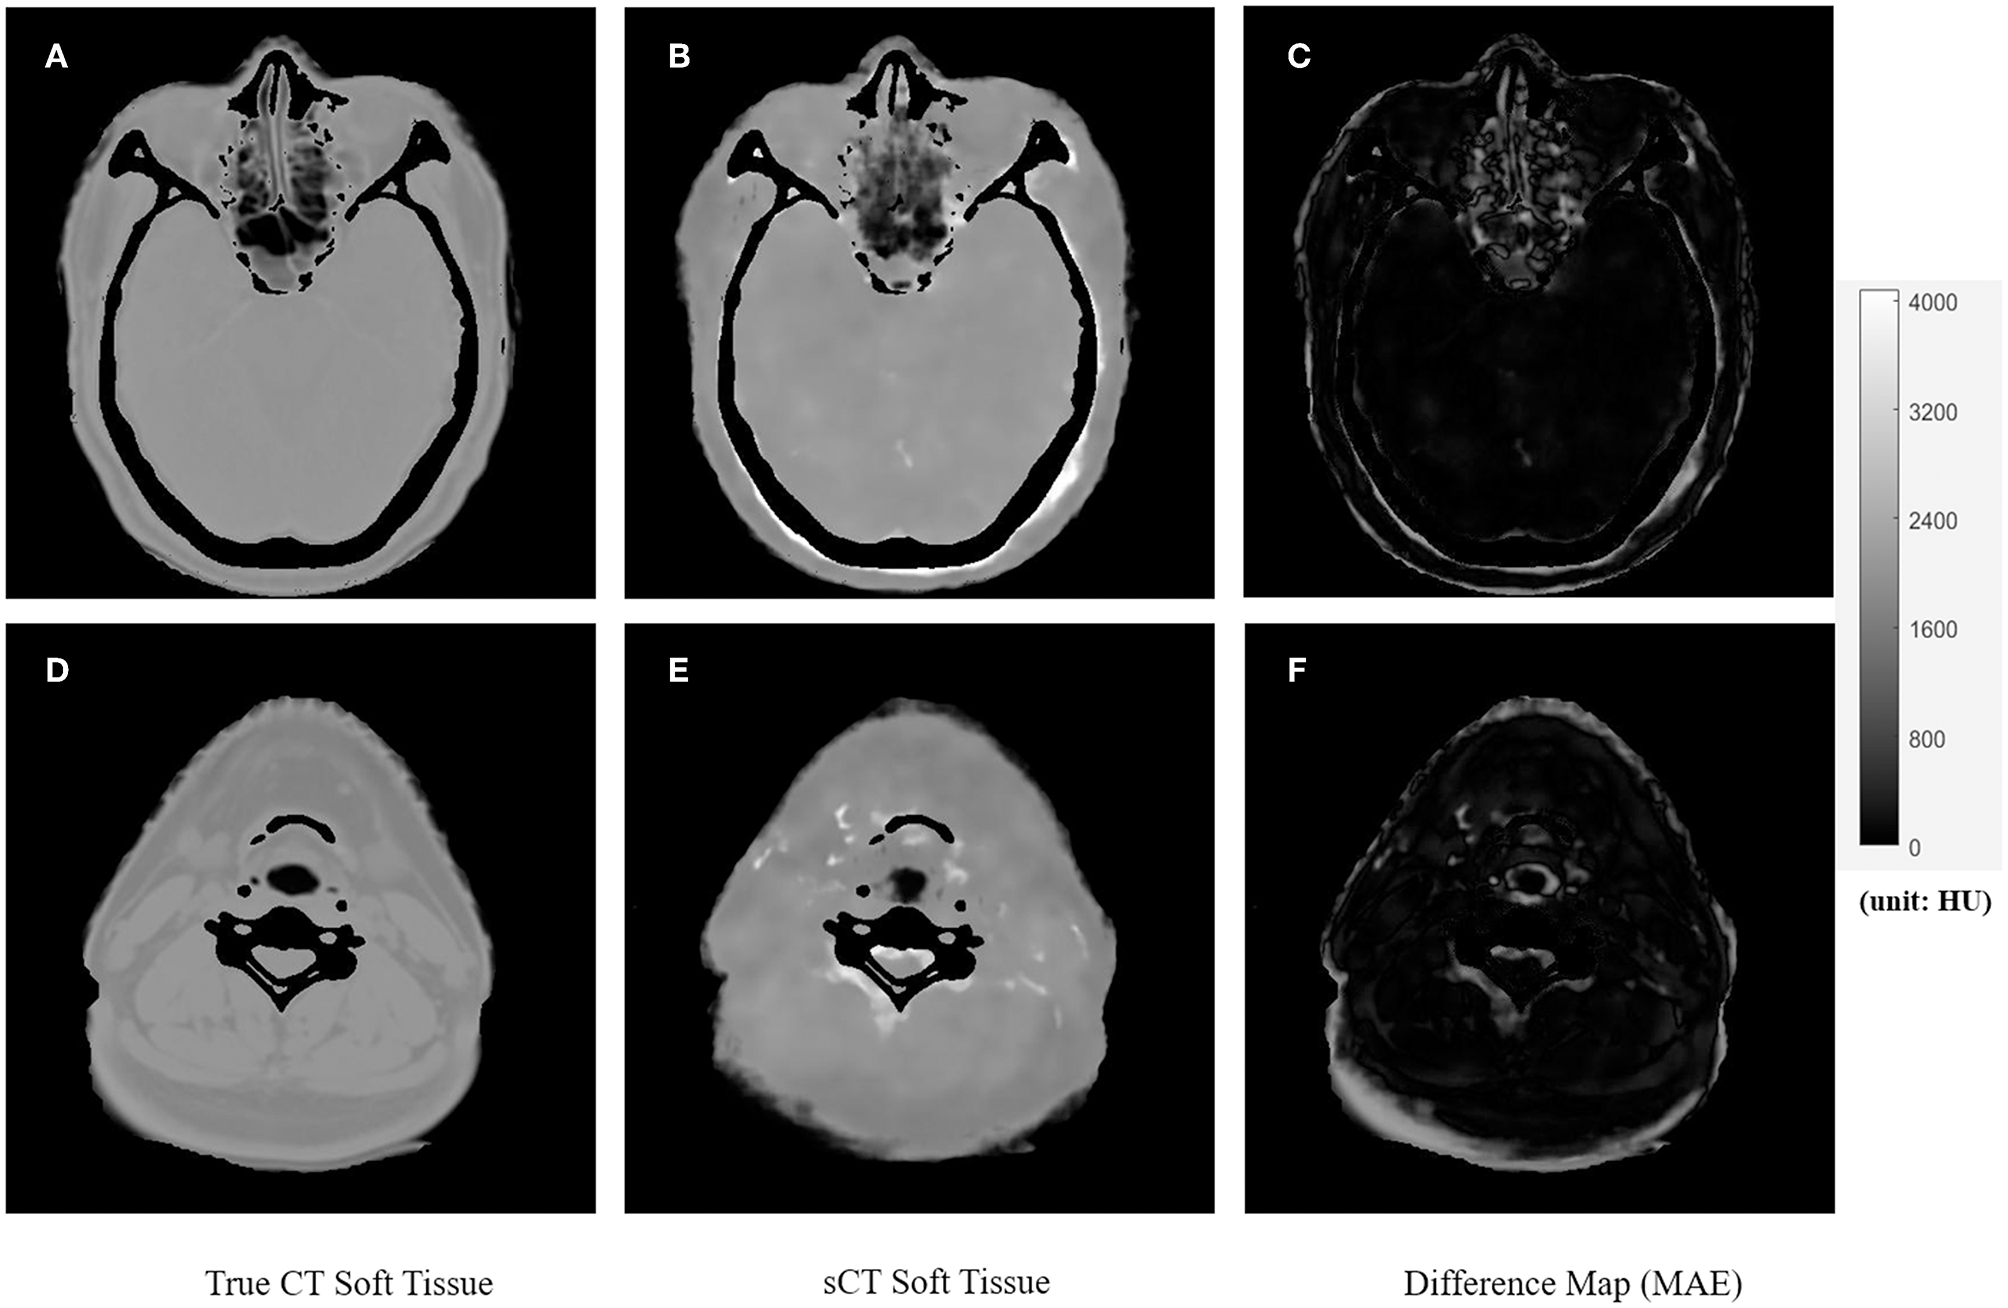

Figures 4, 5 showed the axial view for bone and soft tissues, respectively. The bone structures in synthetic CTs was well-reconstructed by our model, such as the nasal bone (Figure 4E) and bone marrow (Figures 4B,E). The soft tissues in synthetic CTs had the similar intensity as the real ones (Figures 5B,E). However, the interface between bone and soft tissues had higher deviation, and the delicate structures in nasal cavity were blurred in the synthetic CTs (Figure 5B). The majority soft tissue and bone region was reconstructed accurately except the interface between soft tissue and bone and some delicate structures in nasal cavity, where the inaccuracy might be induced by imperfect deformable registration.

Figure 4. The comparison of true CT and synthetic CT for bone. The first column is true CT images. The second column is the synthetic CT images. The third column is the difference maps. (A–C) Showed bone in the neck region. (D–F) Showed bone in the head and nasal region. Gray bar indicated the mapping from CT number to gray scale in the difference maps.

Figure 5. The comparison of true CT and synthetic CT for soft tissues. The first column is true CT images. The second column is the synthetic CT images. The third column is the difference maps. (A–C) Showed soft tissue in the head and nasal region. (D–F) Showed soft tissues in the neck region. Gray bar indicated the mapping from CT number to gray scale in the difference maps.